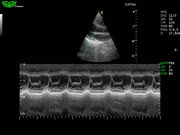

Режимы изображения: B, 2B, B/M, B/BC, CFM, PW, HPRF, PD, направленный PD, CW, режим Color M.

D3P64L 3.0МГц, фазированная решетка.

2.0МГц – 4.4МГц. Применения: кардиология, брюшная полость, акушерство. |